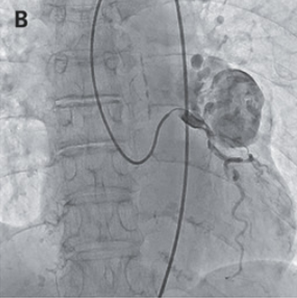

CAGが施行され、左冠動脈から動脈瘤に造影剤が流入し、更に瘻孔を通って肺動脈にも流入していることが示された。